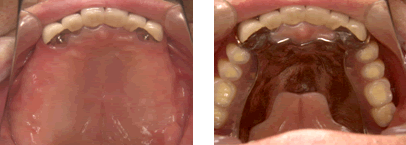

当院では1987年にITIストローマンインプラントによる部分欠損への応用、 また1989年にブローネマルクインプラント用いた無歯顎インプラント治療 (歯がすべてなくなった人へのインプラント治療)を開始しました。

私は歯科医師として患者様にいろいろな治療の選択肢をご提供できるように常に努力をしていきたいと考えており、 インプラント治療はその選択肢の一つだと思います。当院ではより正確に、安全にインプラント手術が行えるようにCTスキャンを応用した診断法を1996年から始めました。 CTスキャンは通常は大きな医科の病院にしか設置されていません。 以前はそういった病院に患者様に行ってもらい撮影をしておりました。 しかし現在では歯科用のCTスキャンが開発され、当院にも2008年4月にプレヴィスタと言うコーンビームCTが設置されました。これによりインプラントのCT撮影、手術シュミレーション検査がいつでもできるようになりました。 難症例を除き、撮影後少しお待ちいただければインプラント治療が可能かどうかご説明できます。患者様もこのCT画像をご覧になると、インプラント治療がどのようなものか良くわかると思います。インプラント治療に関心のある方はお気軽にご相談ください。